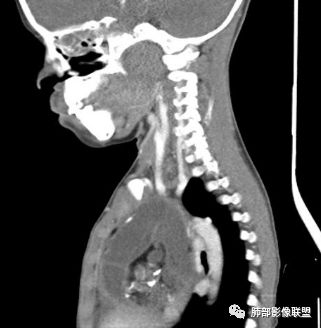

定位:肺内?肺外?

肺侧表面光滑,血管推移

胸膜增厚,朝肺侧稍掀起。

支持肺外